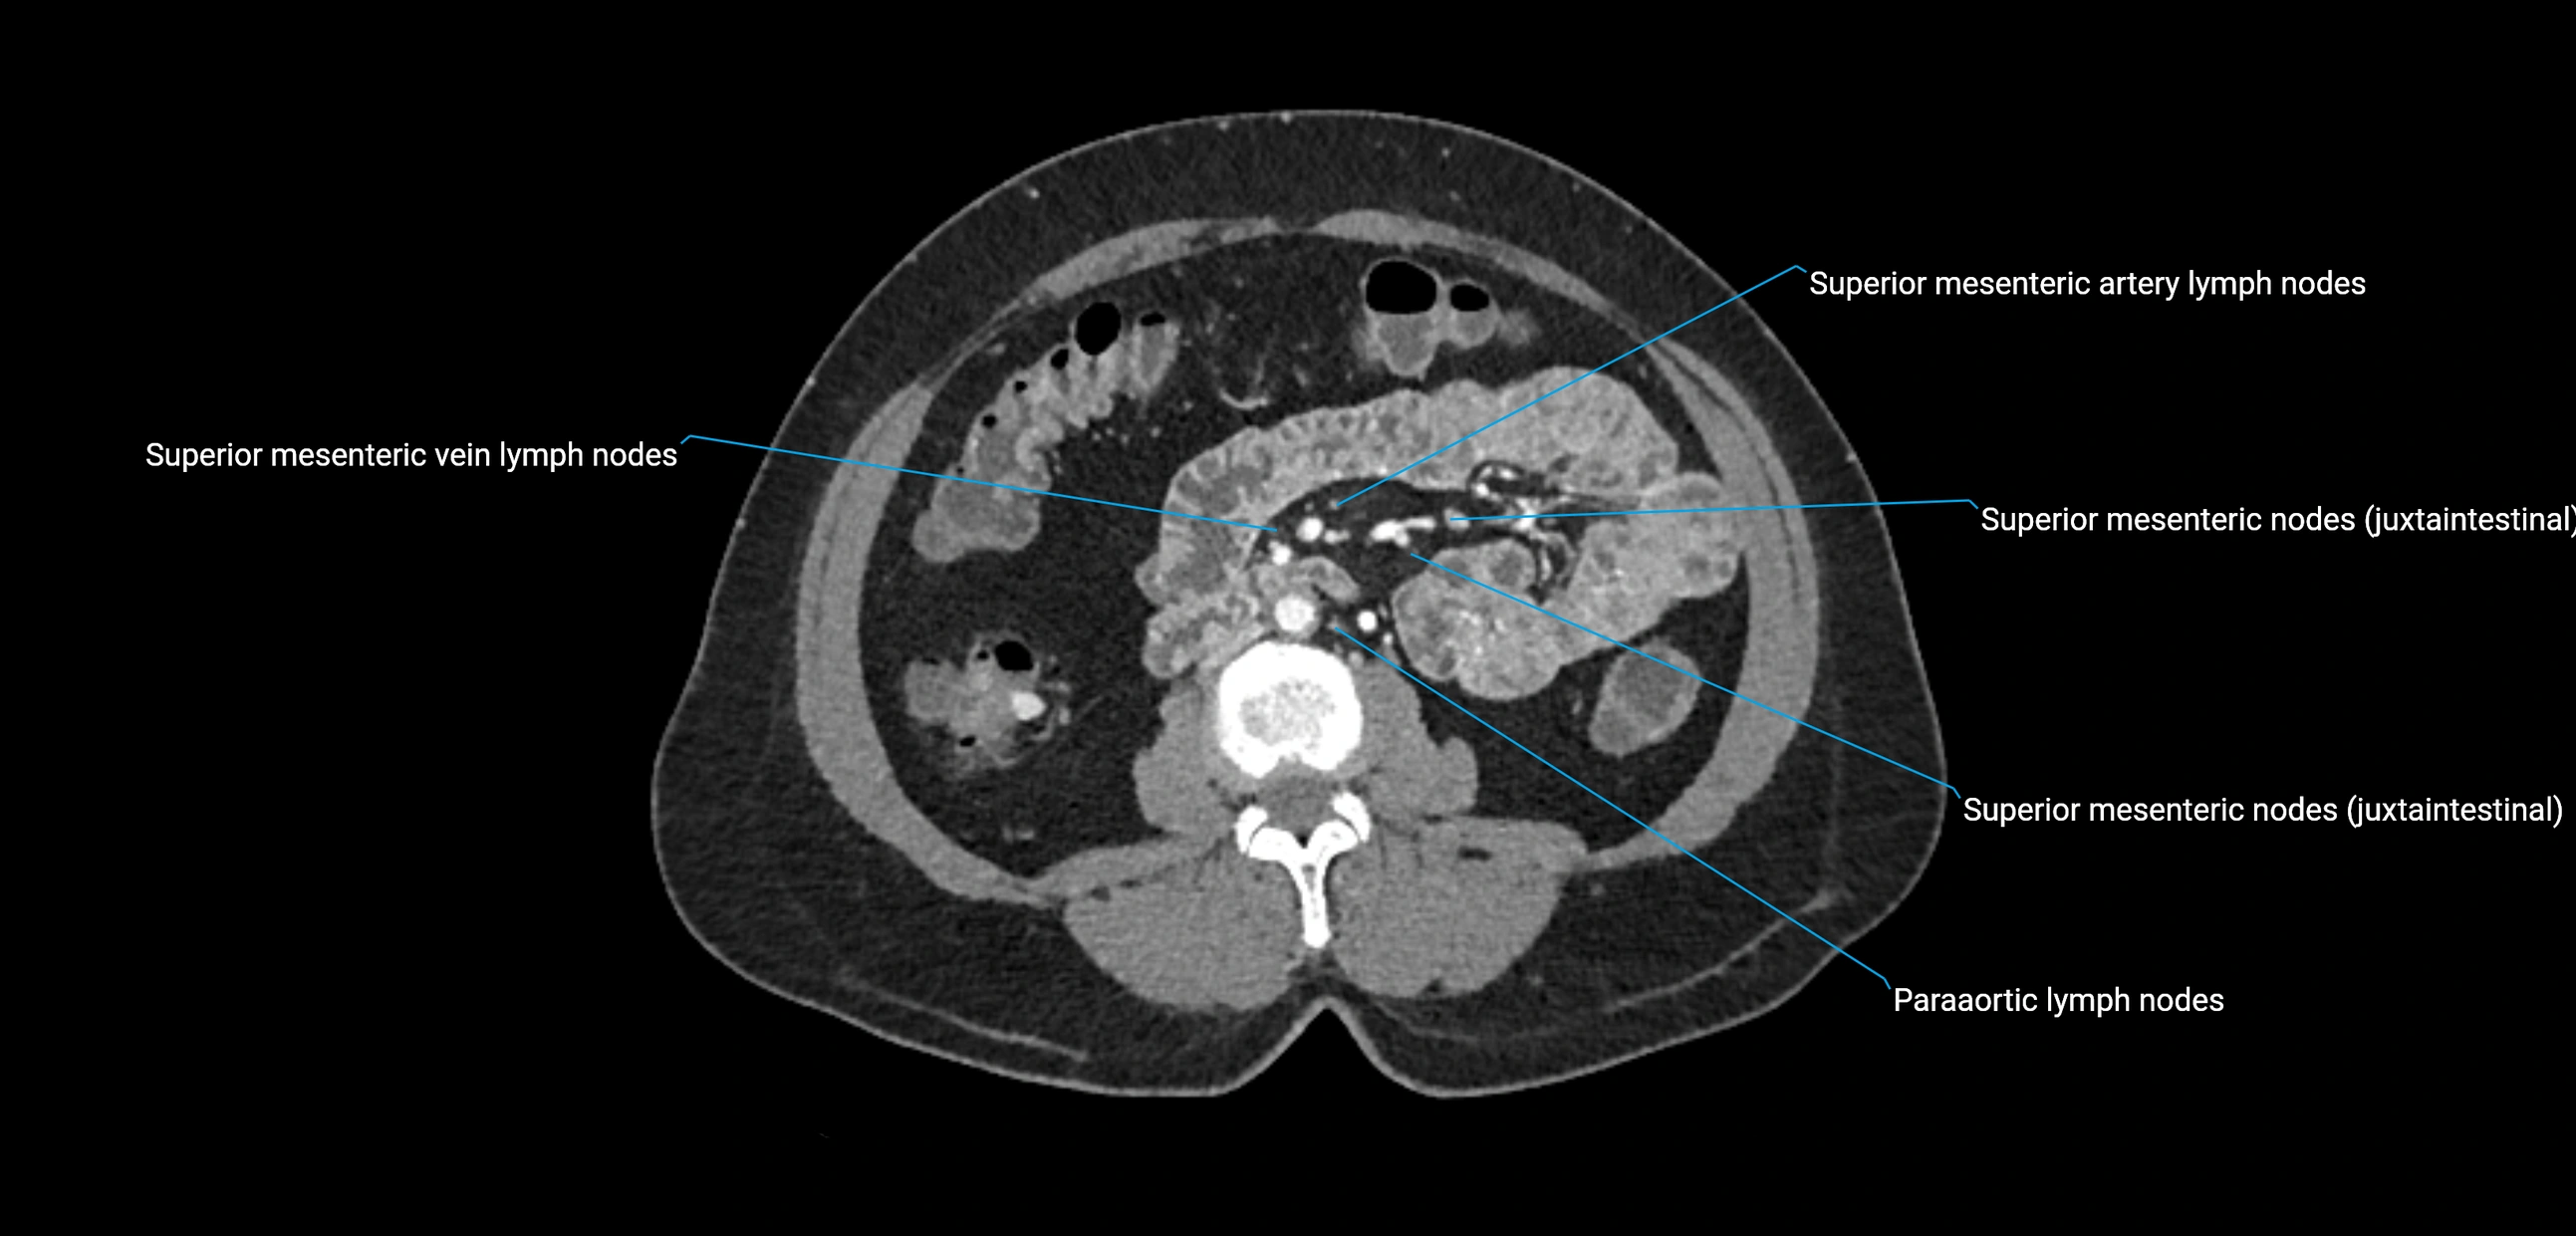

CT image

image